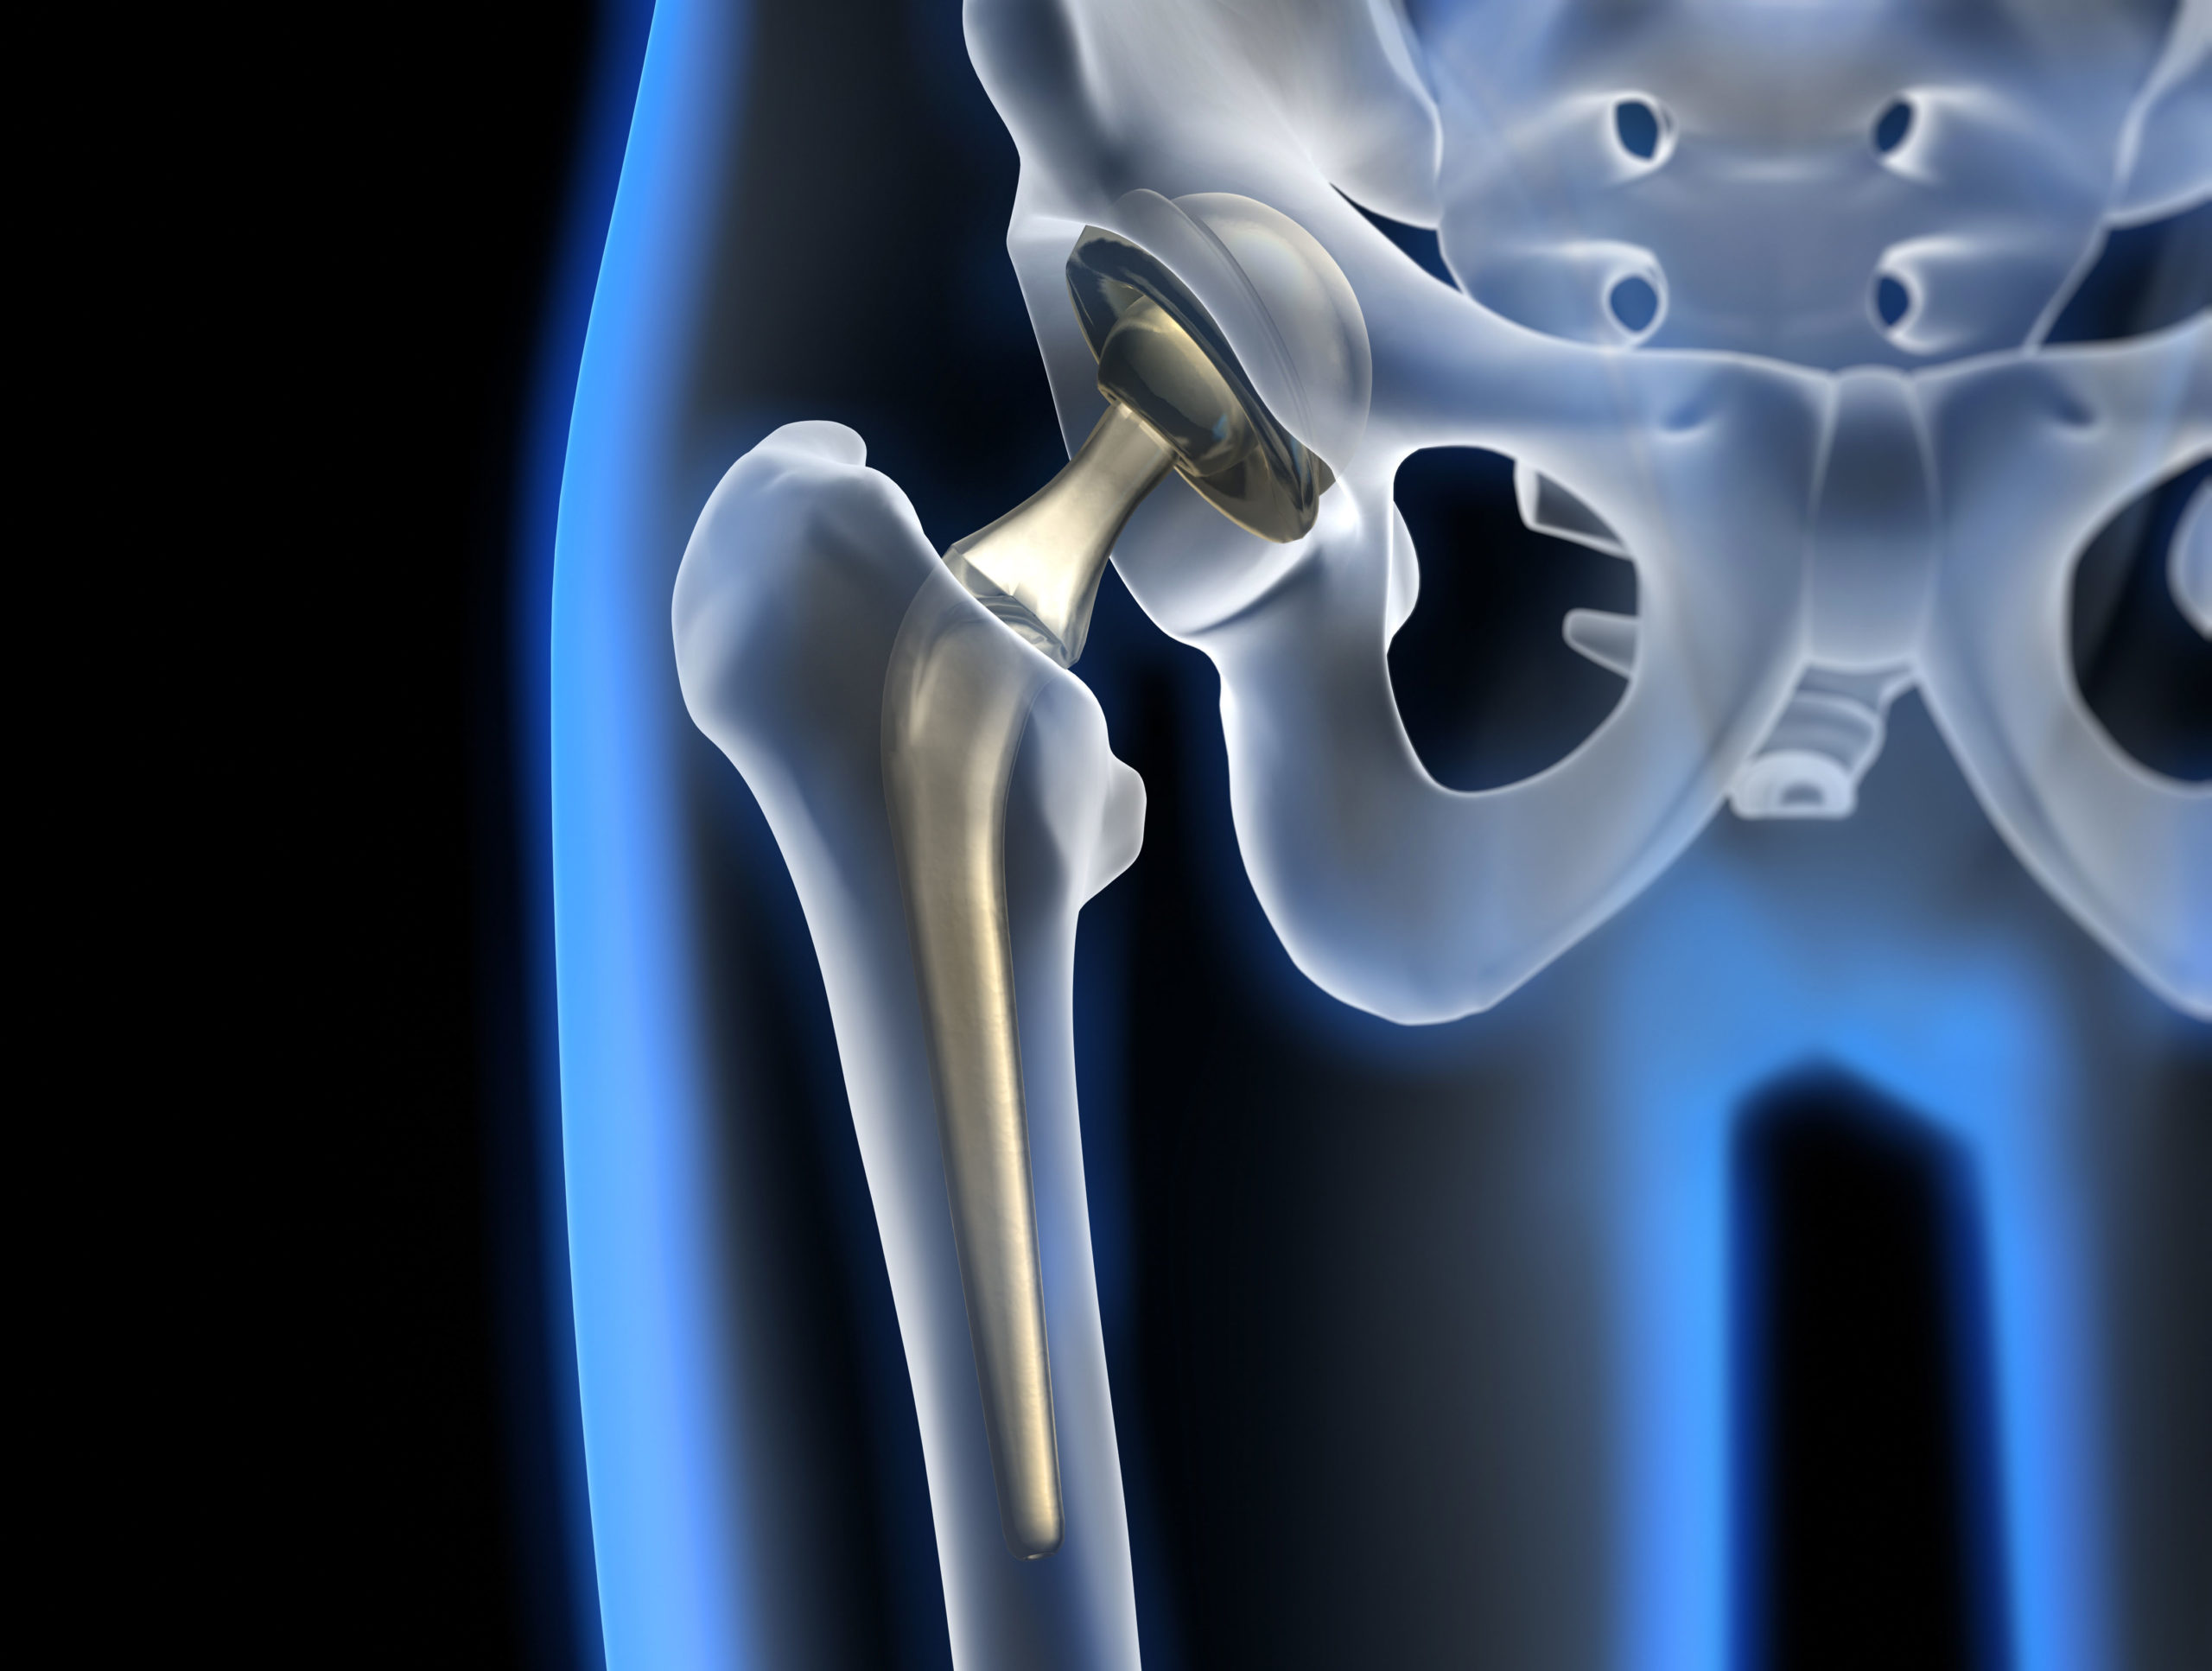

:max_bytes(150000):strip_icc()/x-ray-illustration-of-hip-replacement-1254389829-281a949198324333972a407cc2e90760.jpg)